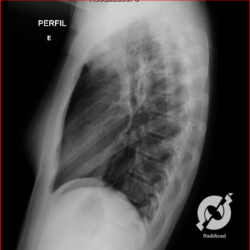

E o nome dado a esta alteração radiográfica que corresponde à substituição do ar alveolar por líquido é a consolidação alveolar.

Uma consolidação alveolar é, por definição, uma opacidade (imagem densa, branquinha) homogênea ou às vezes heterogênea (pela presença de calcificações ou cavidades), de limites mal definidos, exceto quando toca a pleura da parede ou das cissuras pulmonares. É um termo usado tanto em radiografia, como em tomografia computadorizada. Na tomografia, um outro termo é usado: vidro fosco, que é uma opacidade (branquinha mas não tanto como a consolidação), que borra o pulmão mas deixa ver os vasos de permeio (igual bigode de adolescente: dá pra ver todo o fundo).

Nós vamos mostrar aqui um pequeno apanhado de pneumonias de variados agentes, em diversos segmentos e lobos pulmonares, com extensões variadas. O objetivo é identificar o padrão radiológico de consolidação alveolar e não determinar o agente infeccioso, isso vai ser assunto para mais adiante. Aliás já antecipo que é fundamental saber localizar a lesão, porque alguns destes bichos gostam de determinados segmentos, alguns tumores também têm as suas preferências, então localização é fundamental. Se localização não fosse importante, um apartamento na beira do mar sairia o mesmo preço de um apartamento de frente pra BR-101, concordam?

Seguem alguns dos nossos casos de pneumonia para vocês treinarem os olhos e não se apavorarem nos plantões.